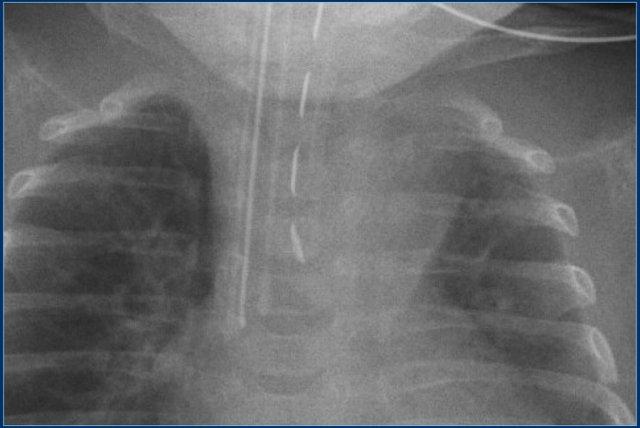

Đường truyền động mạch rốn (4)

Hãy quan sát kỹ hình ảnh trước.

Sau đó tiếp tục đọc.

Các phát hiện bao gồm:

- Đường truyền động mạch rốn ở vị trí quá sâu, đầu catheter nằm tại quai động mạch chủ.

- Đường truyền tĩnh mạch rốn với đầu catheter nằm trong nhánh tĩnh mạch cửa phải.